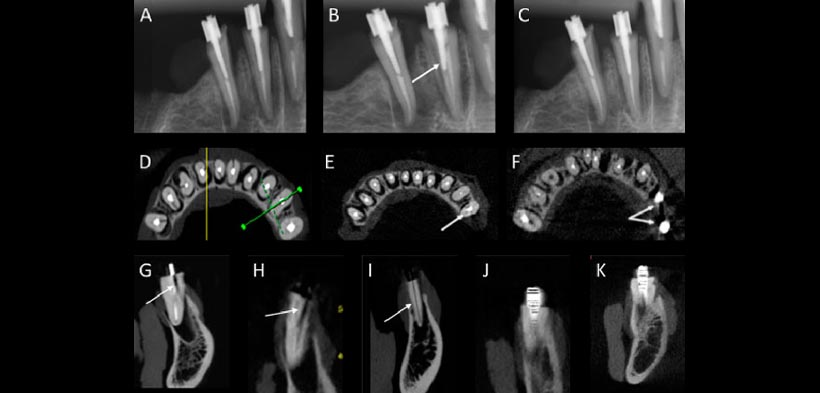

Las ventajas del sistema CBCT como un recurso complementario a exámenes radiográficos convencionales en la planificación y el diagnóstico están bien establecidas en la endodoncia, especialmente en situaciones clínicas complejas en las que los beneficios son mayores que los riesgos potenciales. En estas situaciones, los exámenes CBCT pueden mejorar la exactitud de un diagnóstico. Sin embargo, los artefactos de imagen debido a la presencia de materiales radiopacos en el área de interés son una limitación de esta tecnología. Los dientes endodónticamente tratados con espigos metálicos producen mucho artefacto que no permiten una evaluación adecuada de los trazos de fracturas (fig 1); la presencia de artefactos influye en la interpretación de los resultados, lo que plantea dudas sobre la validez de los pacientes que examinan utilizando CBCT. Una relación de costo-beneficio puede ser justificada solamente cuando los estudios demuestran que estas pruebas tienen una alta sensibilidad y especificidad y contribuyen eficazmente a un diagnóstico.

Figura 1. (a) radiografía ortoradial. (B) la radiografía Distoradial en el que la flecha muestra la fractura radicular vertical (VRF). (C) incidencial mesial (D) tomografía de haz cónico (CBCT) vista axial. (E) CBCT vista axial en la que la flecha muestra artefactos asociados con un espigo metálico, que imitan la VRF en un diente sin VRF. l (F) CBCT vista axial en el que las flechas muestran la presencia de artefactos metálicos Que están asociados con los espigos metálicos. (G, H) CBCT vistas sagital en el que las flechas muestran VRFs. (I) La vista sagital de la CBCT muestra la VRF. (J, K) CBCT en las vistas transversales muestran a los artefactos asociados con los esigos metálicos.